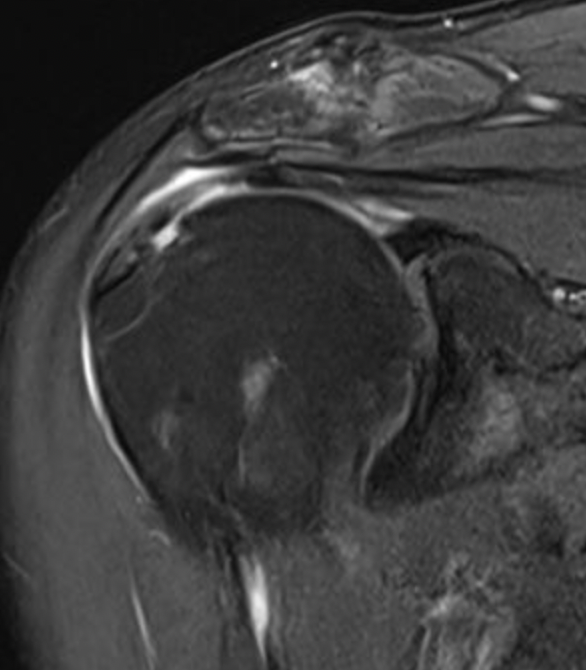

Full thickness rotator cuff tears

Partial bursal sided tear Partial articular sided tears

Small full thickness rotator cuff tear of supraspinatus - retracted to footprint

Large full thickness tear of supraspinatus and infraspinatus tendon - retracted to midhumeral head

Massive rotator cuff tear of the supraspinatus and infraspinatus tendon - retracted to glenoid